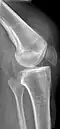

![]() | |

| An x-ray demonstrating quadriceps tendon rupture. Note the abnormal angle of the patella and soft-tissue swelling marked by the arrow. | |